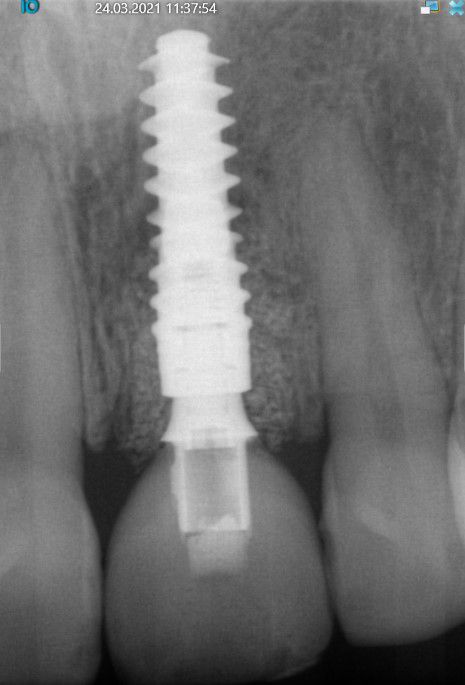

Die klinische sowie radiologische Diagnostik (Abb. 2) ergaben, dass der Versuch des Erhalts von Zahn 21 keine sichere Perspektive bot. Die Entscheidung fiel für die Extraktion des Zahnes. Um das Hart- und Weichgewebe bestmöglich vor der physiologischen Remodellierung nach der Extraktion zu bewahren, wurde eine Sofortimplantation geplant. Mit dem sofortigen Einbringen eines Implantats in die Extraktionsalveole soll einer umfangreichen Knochenresorption und einem starken Weichgeweberückgang vorgebeugt werden [7, 1, 5]. Zudem ist bei einem lappenfreien Vorgehen das chirurgische Trauma gering, was dem ästhetischen Ergebnis (keine Narbenbildung) zugutekommt. Letztlich sind die vergleichsweise schnelle prothetische Rehabilitation und die reduzierte Anzahl von Behandlungssitzungen Argumente für dieses Therapieprotokoll.

Extraktion und Insertion

Unter Lokalanästhesie wurde der beherdete Zahn 21 extrahiert und hierbei auf die maximale Schonung der vestibulären Lamelle geachtet. Die Entzündung konnte rückstandslos entfernt werden. Die Sondierung ergab eine intakte faziale Knochenlamelle (Abb. 6). Die frische Extraktionsalveole wurde als Implantatbett aufbereitet und das Implantat (BLX ø 4 mm, 14 mm) entsprechend der Planung dreidimensional im palatinalen Bereich der Alveole inseriert [3, 6] (Abb. 7 und 8). Das BLX-Implantat hat einige Besonderheiten im Design. So nimmt beispielsweise das Gewinde des Implantats zum krestalen Bereich hin an Stärke zu, sodass zusätzlich zur horizontalen Kondensation auch vertikal Knochen kondensiert wird. Ziel ist eine Primärstabilität im gesamten Implantatbett basierend auf einer homogenen Krafteinleitung. Drucknekrosen sollen so verhindert werden. Im krestalen Bereich ist das Implantat um 1/10 reduziert, um das sensible Gewebe in der Kortikalis drucklos zu lassen. Das BLX-Implantat konnte mit einer für die Sofortversorgung ausreichenden Primärstabilität (mind. 45 N/cm2) inseriert werden.